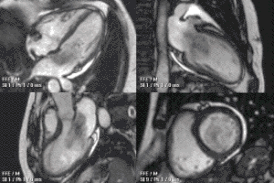

![]() Анимированное МРТ сердца демонстрирует большую миксому, пролабирующую из предсердия в желудочек и обратно через митральный клапан. | |